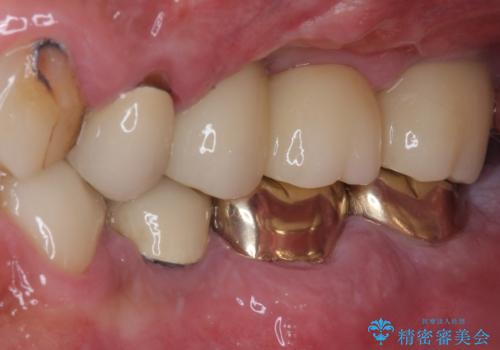

インプラント埋入時に植立具合の安定性を測定したところ、十分な数値が得られたため、速やかに仮歯を装着して咬合回復をさせることができました。

抜歯を含めた外科処置を1回に抑えることができ、あっという間に治療を終えることができました。